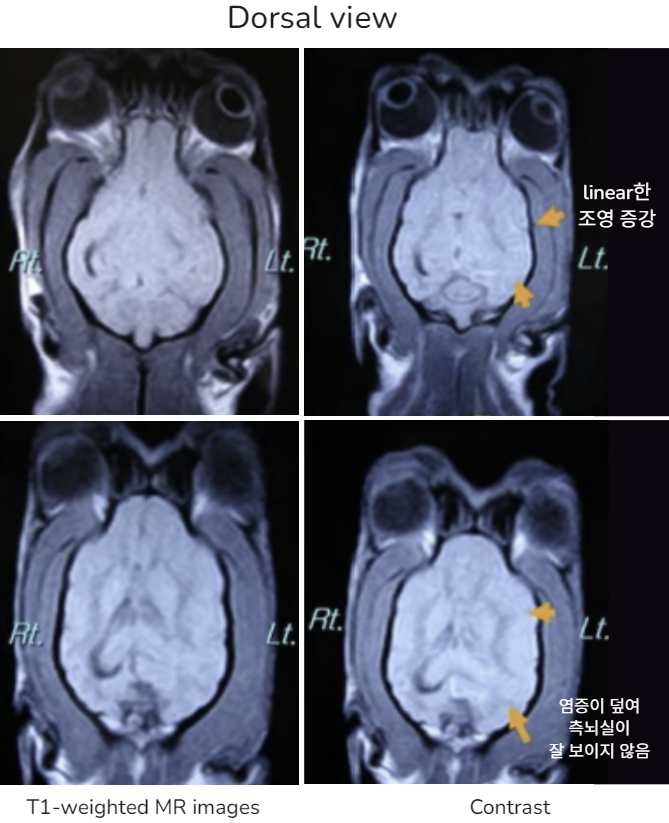

| MRI | |

![]() | ์ผ์ชฝ ๊ฐ์ชฝ๋์ค ์ ๋ณด์. ์ผ์ชฝ ๋ ์ ์ฒด์ ์ฌํ ์ผ์ฆ์ฑ ์๊ฒฌ |

![]() | ๋์ฒ์์ก ์ธ์ ๋ถ๋ถ์์๋ signal ์ฆ๊ฐ ๋๋ ์ ์ฒด์ multifocalํ ์ผ์ฆ ๋ฐ์ |

![]() (๋ชจ๋ฅด๊ฒ ๋ค๊ณ ? ๋๋ ๊ทธ๋..) | ์ผ์ชฝ์์ ๊ฐ์ชฝ๋์ค ์ ์ ๋ณด์, ์ผ์ฆ์ ์ํ edema. linearํ๊ฒ ๊ตญ์์ ์ธ ์กฐ์ ์ฆ๊ฐ โ ํ๊ด์ ์ผ์ฆ์ ์๋ฏธ * solitary, ๋ช ํํ๊ฒ ๊ตฌ๋ณ๋๋ ์กฐ์ ์ฆ๊ฐ โ ์ข ์ * linear/diffuse ํํ์ ์กฐ์ ์ฆ๊ฐ โ ํ๊ด ์ผ์ฆ |